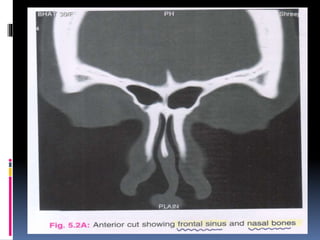

CORONAL CUTS

 One should study the scout film first

The coronal cuts should be read from

anterior to posterior.

The most anterior cuts show frontal sinus

and nasal bone.